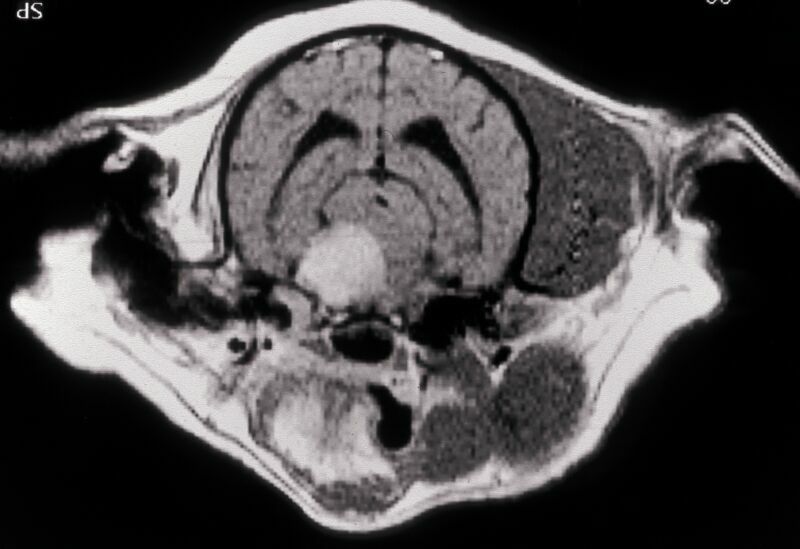

Kernspintomographie Augen-Tierarztpraxis